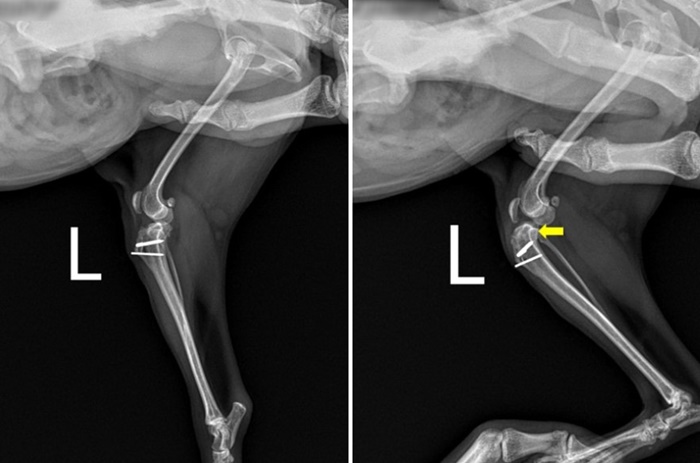

정형외과 검사 상 왼쪽 십자인대 단열을 추정할 수 있는 왼쪽 무릎 관절의 부종 및 Tibial compression test와 Cranial drawal test 양성 반응이 확인됐습니다.

방사선 검사 상 정형외과 검사 결과와 동일하게 십자인대 질환을 의심할 수 있는 왼쪽 무릎 관절의 염증 소견, tibial compression test 시 경골의 전방 변위가 확인됐습니다.

공주는 4년 전, 타병원에서 슬개골 내측탈구 교정수술을 받았던 아이였고, 경골조면변위술 후 4년이 지났음에도 방사선 상 뼈 절골면의 완전한 유합 소견이 보이지 않은 상태로, 경골 조면을 이식한 부위의 골 피질과 절골편의 유착으로 붙어있는 상태라 고려됐습니다.